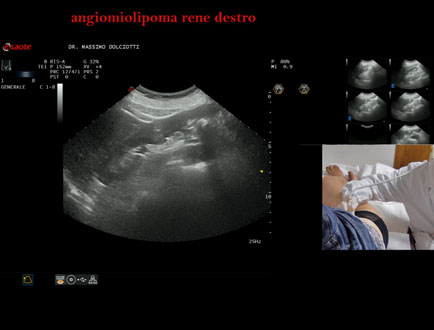

Motivazione dell'esame: riscontro occasionale

Commento all'esame: le immagini ed il video documentano, a al polo superiore del rene destro, immagine iperecogena, delle dimensioni di 25,9 x 23,7 mm, da ricondurre a grande angiomiolipoma.

Conclusioni: grande angiomiolipoma al rene destro (large angiomyolipoma in the right kidney).